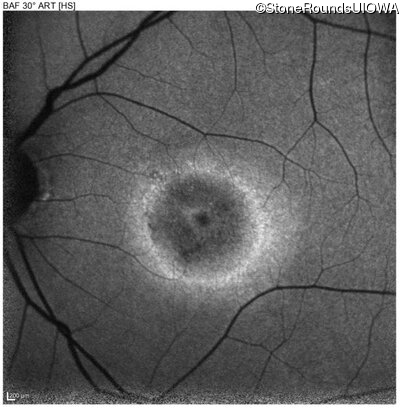

Age at visit: 40 years

OD OS

This 40 year old woman first noticed a reduction of her visual acuity about two years ago. She has been sensitive to light for as long as she can remember.

Diagnosis & molecular findings

Disease Gene Allele 1 variant(s) Allele 2 variant(s) Inheritance mode

AD Stargardt Disease PROM1 Arg373Cys CGC>TGC   AD